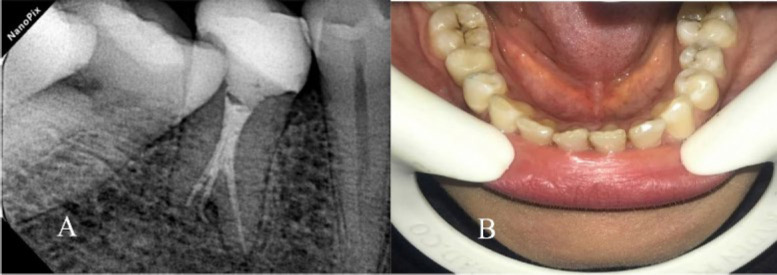

全面了解根管形态是成功进行牙髓治疗的关键。尽管有报道称下颌第二前磨牙的根尖通常只有一个根管,但在本病例中,我们却发现一颗下颌第二前磨牙有三个根管,而且形态呈陶土状。一名患者被转诊至马什哈德牙科学院牙髓科,主诉是下颌右侧第二前磨牙疼痛。牙髓坏死和慢性根尖牙周炎的诊断已经确定。最初的 X 光片显示她的前臼齿有两个牙根。然而,在锥形束计算机断层扫描的辅助下,确诊有三个根管。使用牙科手术显微镜成功地完成了根管治疗过程。使用锥形束计算机断层扫描和牙科手术显微镜极大地促进了牙齿形态的确定,并成功地进行了非手术根管治疗。

A complete understanding of canal morphology is essential to achieve successful endodontic treatment. Although mandibular second premolars are reported to have usually only one root canal at the apex, in this case we reported a mandibular second premolar with three root canals and taurodont morphology. A patient was referred to the endodontic department at Mashhad Faculty of Dentistry with a chief complaint of pain in her mandibular right second premolar tooth. The diagnosis of pulpal necrosis and chronic apical periodontitis was established. The initial radiograph showed a taurodont premolar with two roots. However, with cone-beam computed tomography assistance, three root canals were confirmed. The root canal treatment process was successfully managed with a dental operating microscope. Using cone-beam computed tomography and a dental operating microscope greatly facilitated the determination of tooth morphology and successful following nonsurgical endodontic treatment.